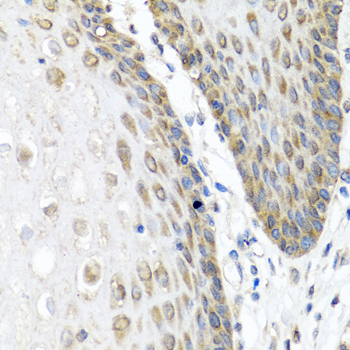

Immunohistochemistry of paraffin-embedded human esophagus using ANGPT1 at dilution of 1:100 (40x lens).

,